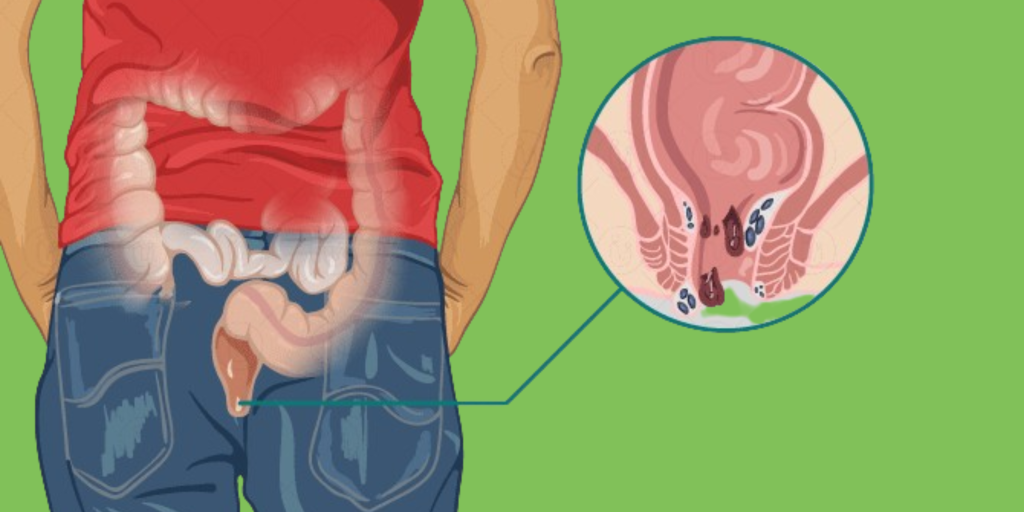

Wasir atau ambeien adalah kondisi pembengkakan pembuluh darah di area anus yang kerap menimbulkan rasa nyeri, gatal, hingga munculnya benjolan yang mengganggu aktivitas sehari-hari.

Banyak penderita wasir yang mengalami kesulitan buang air besar, duduk terlalu lama, bahkan berdarah saat buang air. Kondisi ini perlu penanganan yang tepat dan tidak bisa dibiarkan terlalu lama.

Wasir bisa terjadi akibat berbagai faktor seperti sering mengejan, kebiasaan duduk terlalu lama, kekurangan serat, serta gaya hidup kurang aktif. Gejalanya meliputi rasa panas atau nyeri di anus, keluarnya darah saat buang air besar, hingga benjolan di sekitar anus. Jika tidak segera Anda tangani, wasir bisa berkembang menjadi lebih parah dan mengganggu kualitas hidup.